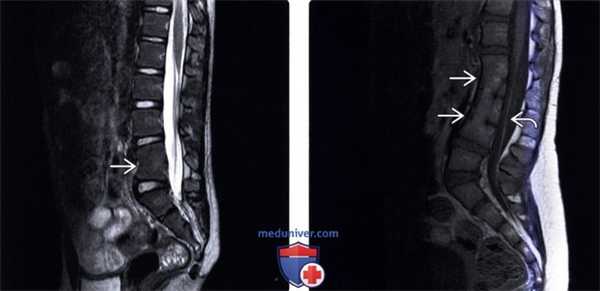

(Слева) На рентгенограмме пояснично-крестцового отдела в прямой проекции (исследование выполнено по поводу болевого синдрома в нижней части спины) случайной находкой стало неполное заращение пластинки дуги S1.

(Справа) На аксиальном Т1-ВИ видно типичное неполное слияние задних элементов позвонка по срединной линии. Эта находка стала случайной в ходе проведения обследования пациента по поводу болевого синдрома в нижней части спины. (Слева) КТ, фронтальный срез: признаки косого асимметричного расположения пластинок дуги L5 позвонка, наслаивающихся друг на друга, — та -кая конфигурация приводит к ротационной перегрузке дугоотростчатых суставов и преждевременной их дегенерации.